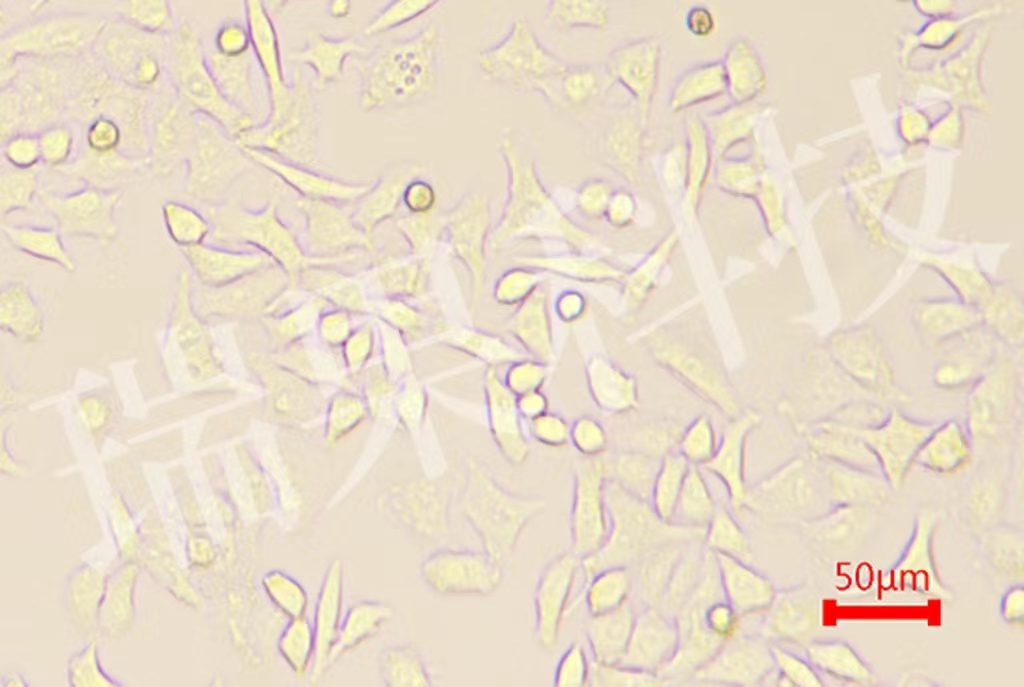

過碘酸-雪夫(Pexiodic acid-schiff,PAS)染色又稱糖原染色。胞漿內(nèi)存在的糖原或多糖類物質(zhì)(如黏多糖、黏蛋白、糖蛋白、糖酯等)中的乙二醇基(CHOH-CHOH)經(jīng)過碘酸(Periodic acid)氧化,轉(zhuǎn)變?yōu)槎┗–HO-CHO),與雪夫(Schiff

過碘酸-雪夫(Pexiodic acid-schiff,PAS)染色又稱糖原染色。胞漿內(nèi)存在的糖原或多糖類物質(zhì)(如黏多糖、黏蛋白、糖蛋白、糖酯等)中的乙二醇基(CHOH-CHOH)經(jīng)過碘酸(Periodic acid)氧化,轉(zhuǎn)變?yōu)槎┗–HO-CHO),與雪夫(Schiff)試劑中的無色品紅結(jié)合,形成紫紅色化合物而沉積于胞漿中糖原類物質(zhì)所存在的部位。該反應(yīng)稱為過碘酸-雪夫(PAS)陽性反應(yīng)。